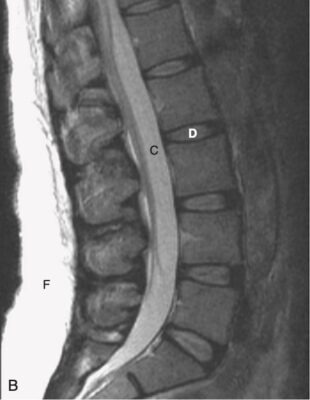

- Trên hình ảnh MRI cột sống đứng dọc T1W, các thân đốt sống, chứa tủy xương, thông thường sẽ có cường độ tín hiệu cao (sáng), các đĩa đệm sẽ có cường độ tín hiệu thấp hơn và dịch não tủy (CSF ) trong túi cùng sẽ có cường độ tín hiệu thấp (tối) (Hình 4, A).

- Trên hình ảnh T2W thông thường, thân đốt sống sẽ có cường độ tín hiệu thấp hơn một chút so với đĩa đệm, trong khi dịch não tủy sẽ sáng (ngược lại của T1) (xem Hình 4, B).

- Xương vỏ có tín hiệu thấp (tối) trên tất cả các chuỗi xung.